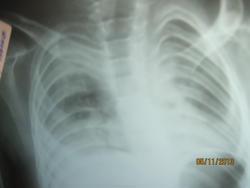

Ребенок находиться в ОРИТ. ДЦП. Диагноз ОРЗ, фарингит. С целью исключения пневмонии направлен на рентген.

8.10.13gpryahin_5let_dcp_verhnedolevaya_pnevmoniya._zavualirovannost_pravogo_sinusa..jpg8.10.13g_pryahin_5let_pravyy_bok.jpg

Cредостение на месте. Написала инфильтрация S1, 2, 3, 5 Пневмония без динамики. Завтра снова хотят контроль делать и рентгена и УЗИ.